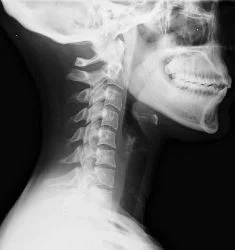

In whiplash, the neck straightens from its normal curvature. This change results in the joints wearing out faster.

Car accidents like this one are way too common and can lead to long term injuries even if there is not an immediate onset of pain. Whiplash causes tears in the muscles and ligaments. Often times, other structures including nerves, discs and bones are also injured. Left untreated, many of these injuries lead to long term chronic pain and underlying damage. Even low speed collisions can cause significant damage.